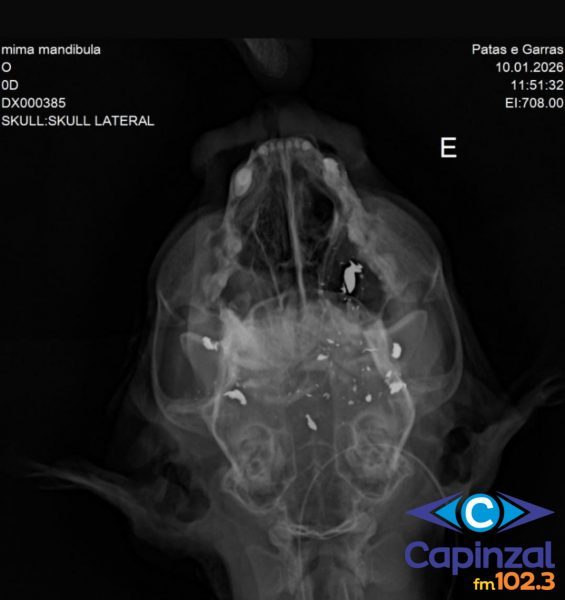

Segundo a entidade, o animal foi atingido por três disparos na região da cabeça. Dois tiros causaram a destruição da mandíbula e o terceiro atingiu o céu da boca, provocando ferimentos considerados fatais.